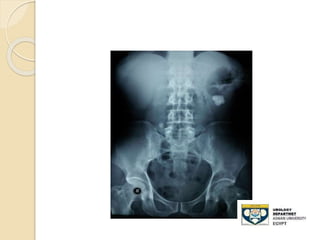

KUB film

 - Advantages:

◦ 80-90% of stones are radio-opaque

◦ Minimal radiation

 Disadvantages:

◦ Radiolucent stone

◦ Easy to miss mid-ureteral stones over the

sacrum

◦ Bowel gas can obscure its efficacy

◦ Cannot differentiate , Stones,Calcified LN

,

◦ Sensitivity: 50-70%

STONE LOWER THIRD URETER